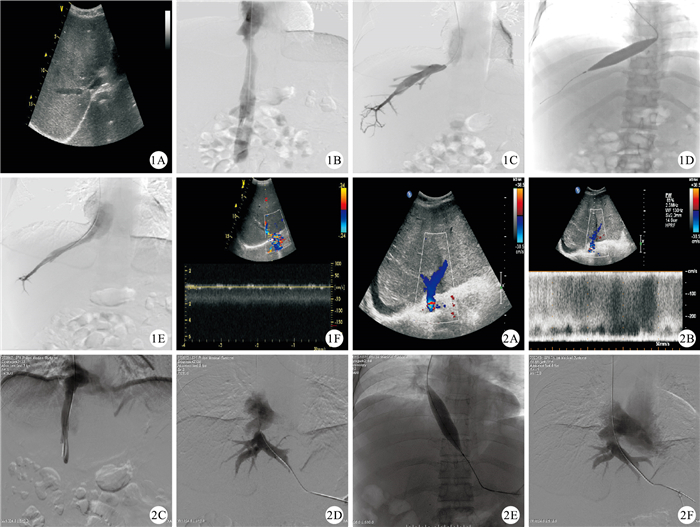

本組94例肝靜脈型BCS患者中,男59例,女35例;年齡15~72歲、(39.83±12.54)歲;病程2周~16年,中位病程為4個月;介入治療前的肝功能Child-Pugh分級結果見表 1。主要臨床表現為腹脹(71例)、納差(42例)、虛弱(30例)、上腹部疼痛(25例)、消化道出血(21例)、黃疸(3例)及肝性腦病(7例);主要體征為腹壁靜脈曲張(14例)、肝臟腫大(64例)、脾臟腫大(41例)、腹水(59)及下肢水腫(16例)。94例患者術前均經彩色多普勒超聲(圖 1和圖 2)、多層螺旋CT或高場強MRI檢查確診,并明確了每支肝靜脈的病變情況、肝靜脈是否合并血栓形成、下腔靜脈(inferior vena cava,IVC)的病變情況、肝靜脈與IVC的空間位置關系及是否合并原發性肝細胞肝癌(HCC)。肝靜脈廣泛閉塞型BCS需要經頸內靜脈途徑行門-腔分流術或開腹行腸-腔分流術者未納入分析。

經頸內靜脈途徑或股靜脈途徑行IVC造影,明確目標肝靜脈的開口位置(圖 1B和圖 2C)。如果同時合并IVC阻塞,首先完成阻塞IVC的開通,具體方法同文獻[3]。

對狹窄性肝靜脈病變,經頸內靜脈或股靜脈途徑引入5F獵人頭導管/Cobra導管至IVC內目標肝靜脈的開口處。將導管對準肝靜脈開口方向后,在導絲的配合下通過狹窄處進入肝靜脈內,完成肝靜脈的開通。經多次嘗試未成功者,經導管引入由球囊內支撐導絲自制而成的、頭端為鈍頭的開通導絲(直徑為0.089 cm,100 cm長),調整方向后進行肝靜脈的開通。若導管進入肝靜脈內,即完成肝靜脈的開通。開通肝靜脈后行肝靜脈造影,明確其阻塞的程度(圖 1C)。若副肝靜脈為目標肝靜脈,當其走行與IVC成銳角時,經頸內靜脈穿刺,完成其開通;而當其與IVC成鈍角時,則經股靜脈穿刺,完成其開通。

1.2.5 球囊導管擴張成形+血管內支架置入術

沿加強導絲引入球囊導管,至肝靜脈阻塞處進行血管內球囊擴張成形(圖 1D和圖 2E)。球囊充分擴張3次,每次持續約2 min。而后退出球囊,行肝靜脈造影以評價肝靜脈的擴張效果,并進行肝靜脈與IVC壓力差的測定(圖 1E和圖 2F)。對于節段性閉塞病變,球囊擴張后,置入血管內支架,而后進行肝靜脈造影以評價肝靜脈支架置入的效果,并進行肝靜脈與IVC壓力差的測定。

所有患者分別于術后1周左右、1個月、3個月及6個月隨訪,以后每隔6個月左右隨訪1次,以觀察癥狀和體征的改善情況。隨訪截止日期為2013年12月12日。隨訪檢查主要包括實驗室檢查和彩色多普勒超聲檢查。實驗室檢查指標以血常規、肝功能及凝血功能指標為主,以了解肝功能的改善情況、抗凝是否達標,以及有無相關出血并發癥發生。影像學檢查以彩色多普勒超聲檢查為主,主要明確目標肝靜脈的通暢情況、有無狹窄或閉塞、管壁是否增厚、是否有血栓再次形成以及肝臟實質情況,特別是有無HCC病變發生(圖 1F)。對彩色多普勒超聲檢查提示有肝靜脈狹窄甚至閉塞病變者,進一步行多層螺旋CT或MRI檢查,如同樣提示肝靜脈閉塞復發,則進行肝靜脈造影并進行再次治療。